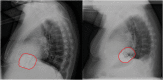

Methods and results: In this retrospective analysis, data from replacement procedures and follow-up visits were collected from all patients who underwent elective S-ICD generator replacement in our tertiary centre from June 2014 until November 2019. Original device position was assessed using the PRAETORIAN score. Complications were defined as those requiring surgical intervention, systemic antibiotic treatment, or device extraction. Seventy-two patients were included, with a median follow-up of 1.9 years (IQR 0.6-3.3 years) after replacement. Battery depletion occurred after 5.9 ± 0.7 years. The pulse generator was repositioned in patients with a PRAETORIAN score ≥90 to minimize the defibrillation threshold. Although there was an increase in impedance compared to the implant procedure, first shock conversion rate during defibrillation testing was 91.4% with a success rate of 100% after multiple attempts. Two patients developed a complication after, respectively, 9 and 21 months, resulting in a complication rate of 1.4% per year.